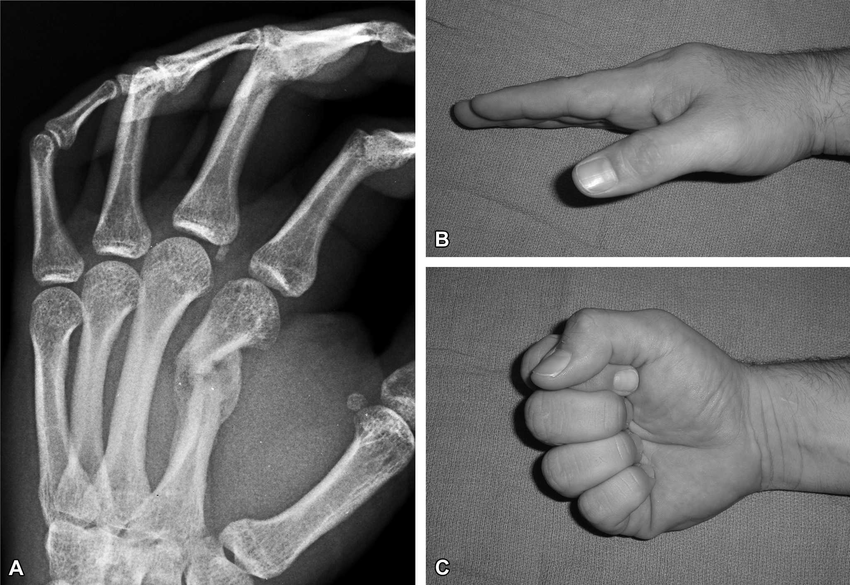

This image demonstrates an early malunion of a second metacarpal fracture (A) and the resulting rotational deformity seen clinically when the patient makes a fist (B-C).

Unlike angulation, even small degrees of rotation are poorly tolerated in the hand. When a metacarpal heals with rotational malalignment, the affected finger deviates from its normal trajectory, producing “scissoring” or overlap of the digits during flexion.

The key lesson is simple 👉 Rotation is a clinical diagnosis.

X-rays may underestimate the deformity, so the finger cascade during fist formation must always be assessed. Persistent malrotation is a common indication for reduction or fixation, as untreated rotational deformity leads to significant functional impairment.